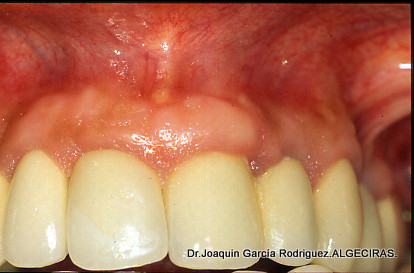

En este caso podemos visualizar las diferencias  evidentes entre una mesoextrutura o prótesis fija sobre implantes y la rehabilitación ceramometálica sobre implantes.

• La prótesis ceramometálica se sustenta entre 8 y 10 implantes para repartir cargas de 14 dientes en cada maxilar. A diferencia de la anterior, aquí los dientes se diseñan a mano, capa a capa por el ceramista.

En este caso clínico mostramos la diferencia entre una Prótesis Hibrida o Mesoextructura y una Rehabilitación ceramometálica.